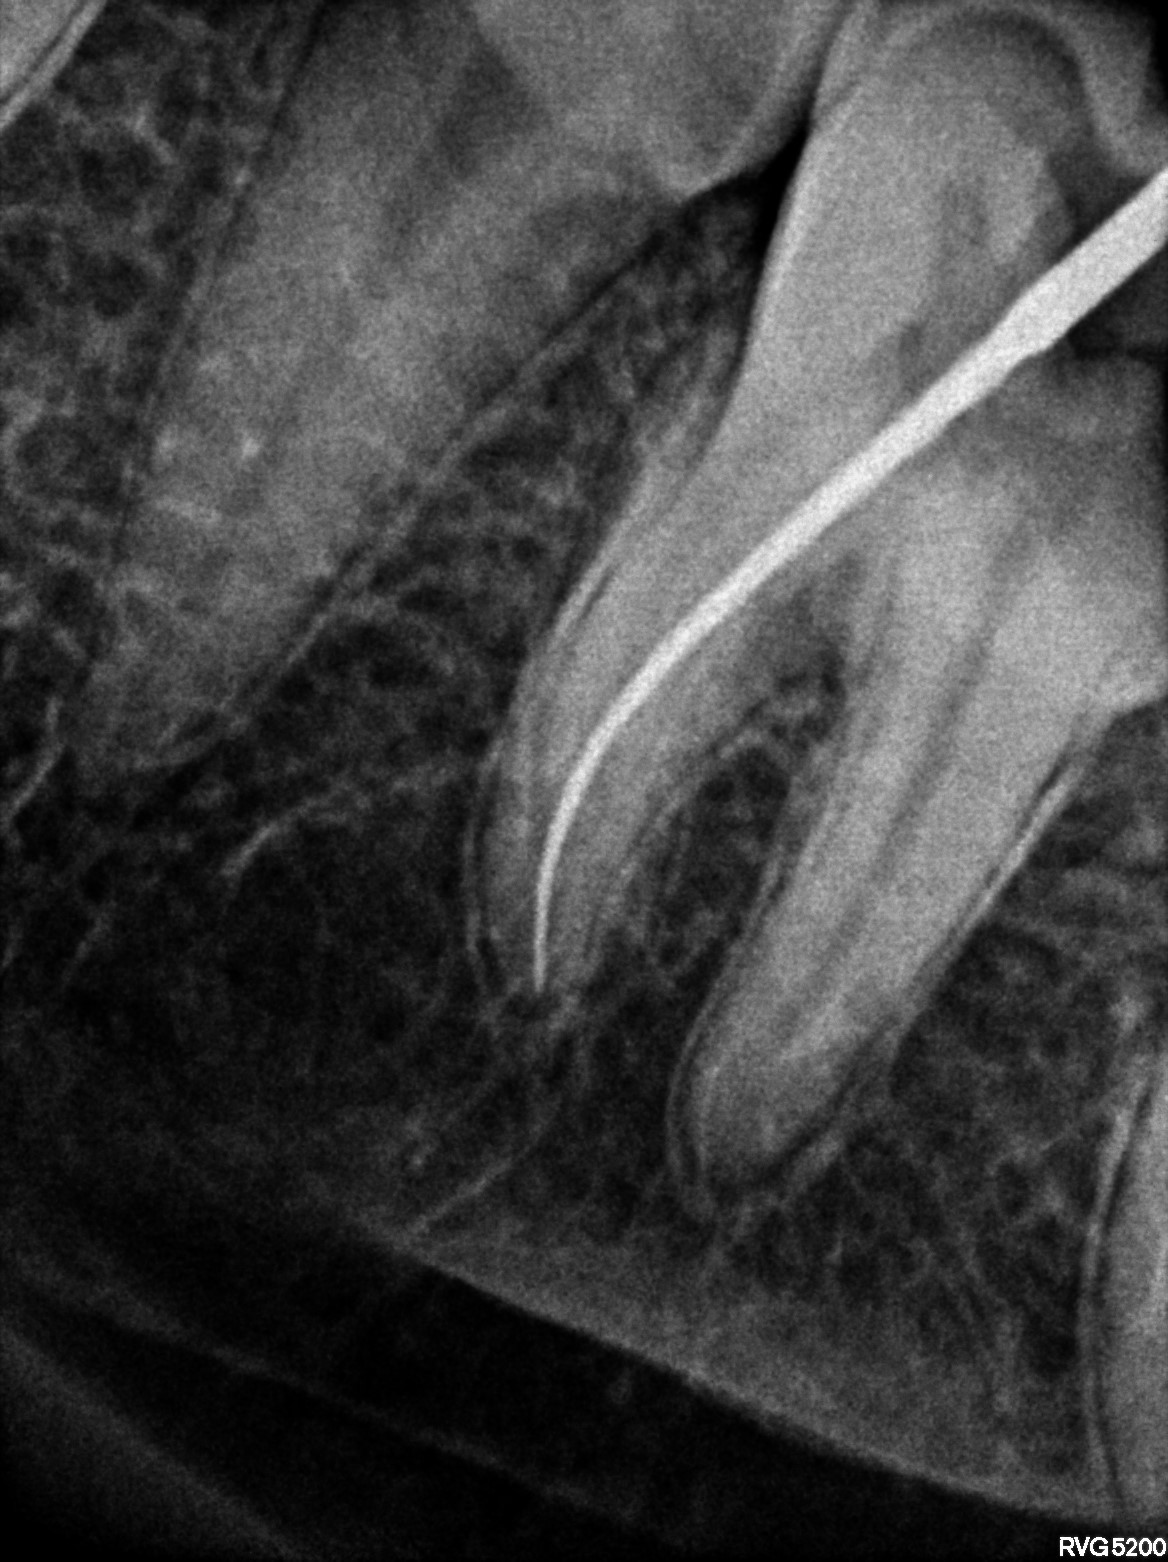

Dental Radiographs FHIR: DocumentReference · LOINC 24641-7

xray_1772613108_3.jpg

24641-7